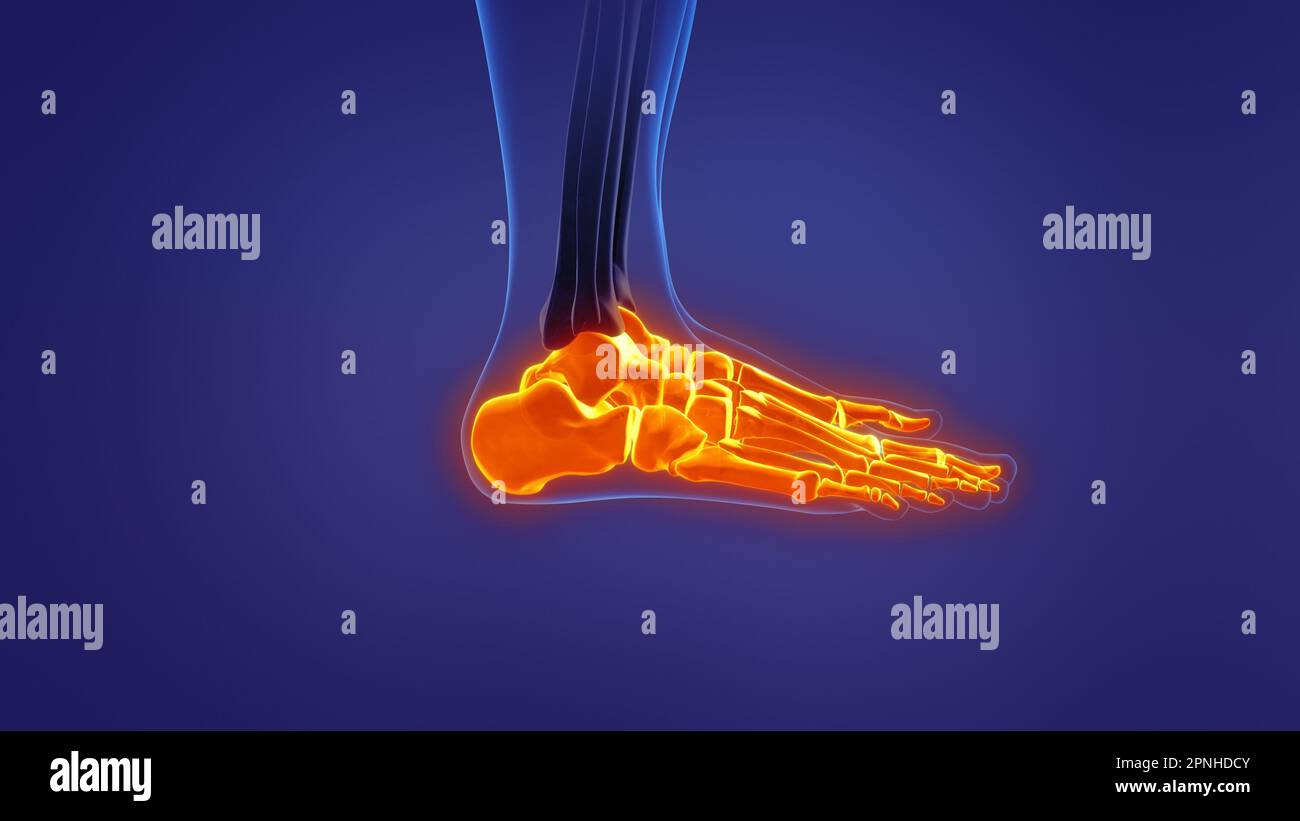

RF2R3WKY1–Illustration médicale des principales parties des os du pied en vue latérale, avec annotations.